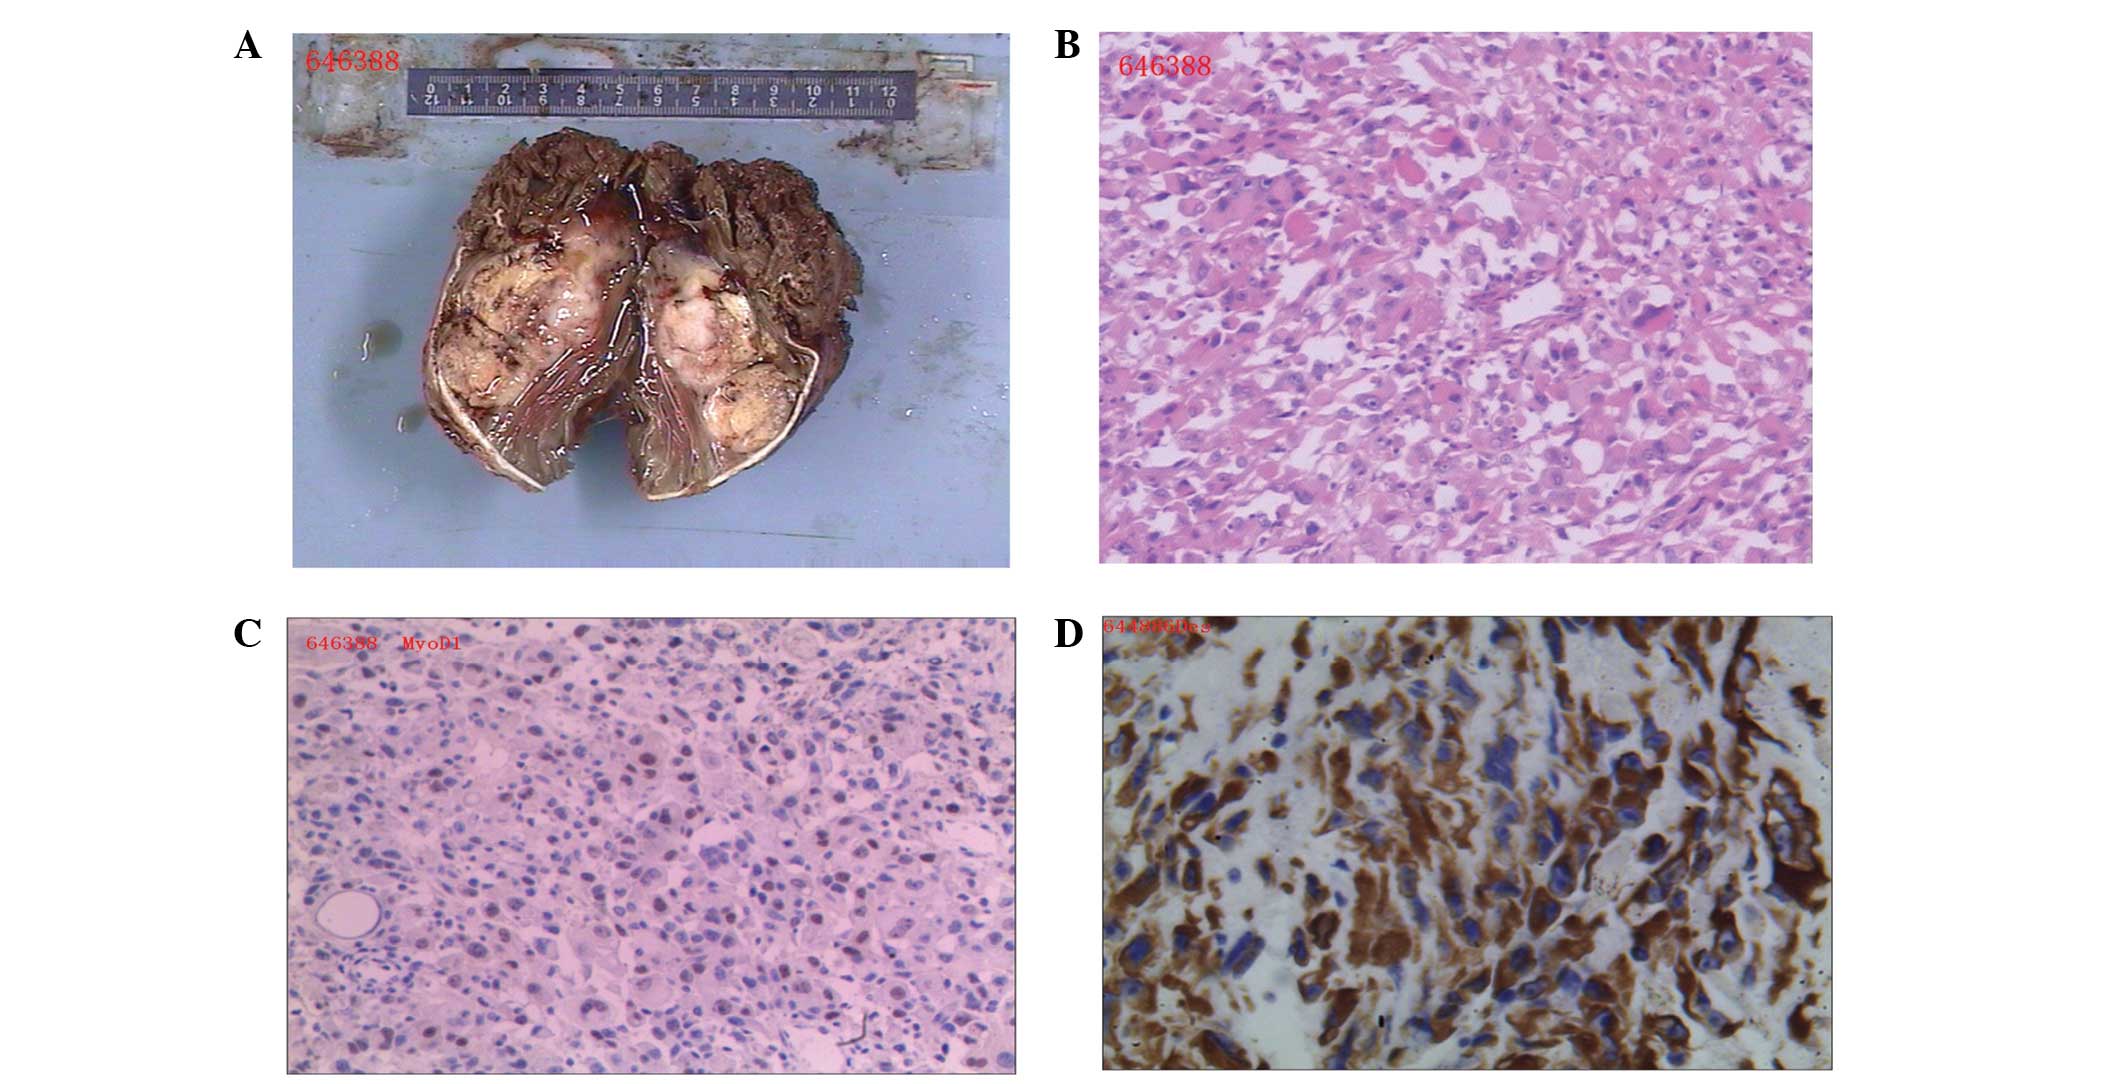

Misdiagnosis Of Primary Pleomorphic Rhabdomyosarcoma Of The Right Thigh

www.spandidos-publications.com

www.spandidos-publications.com

rhabdomyosarcoma thigh pleomorphic axial misdiagnosis primary case adult young right report figure ol

Misdiagnosis Of Primary Pleomorphic Rhabdomyosarcoma Of The Right Thigh

www.spandidos-publications.com

www.spandidos-publications.com

rhabdomyosarcoma pleomorphic thigh case examination gross misdiagnosis primary adult young right report figure ol

Rhabdomyosarcoma pleomorphic thigh case examination gross misdiagnosis primary adult young right report figure ol. Rhabdomyosarcoma femur mri pleomorphic posterior treatment thigh examination mass. Newborn rhabdomyosarcoma leg lower